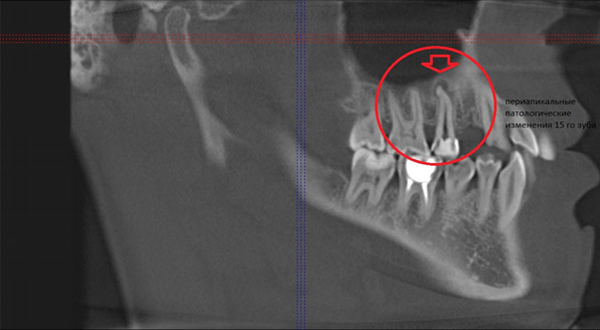

Рентгеновские снимки кариеса корня зуба

Раздел: Визуальные уроки